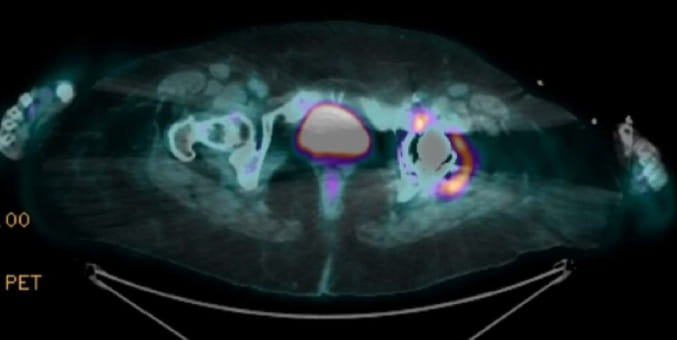

A paciente também apresentava depósitos abundantes de oxalato na pele semelhantes à gota tofácea, mas sem hiperuricemia, como evidenciado nos Painéis C e D). A microscopia de polarização confirmou a presença de oxalato em uma amostra desses depósitos (ver Painel E).